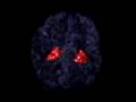

The Auditory Pathways The auditory center, in the brain, shown above in red, is concerned with hea… Tags: ent Dr.Murali Krishna Feb 26, 2009 100 views